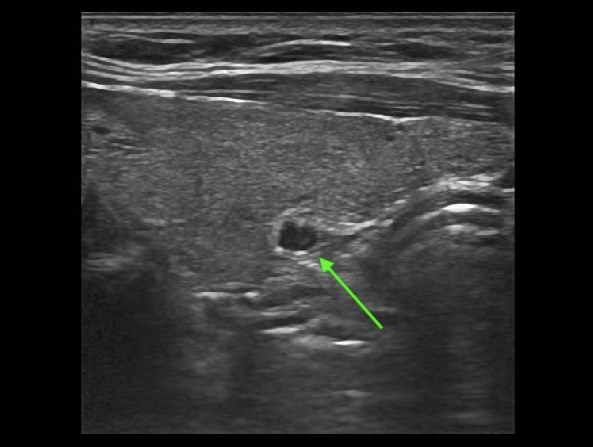

One of our patients from last week visited us from Houston, TX. She had clear biochemical evidence of primary hyperparathyroidism for 3 years, blood calcium was as high as 10.6 with corresponding PTH 120 and Vitamin D 13. She felt lousy. She had bone pain, fatigue, difficulty sleeping, headaches, heartburn, and brain fog. She and her husband wanted to find her old self again. She had an ultrasound at her home doctor’s office suggesting a right middle-thyroid cystic thyroid nodule. This finding led to more questions than answers. She wondered if she had a thyroid nodule that needed intervention. Her home doctor suggested needle-aspiration of the nodule to see if they could obtain more information.

We took one look at the nodule with our standard day-of-surgery ultrasound and confirmed the nodule to be a mixed cystic and solid parathyroid gland, not a thyroid nodule. The patient did not need expensive imaging tests at home, but rather the Norman way in a bad way.